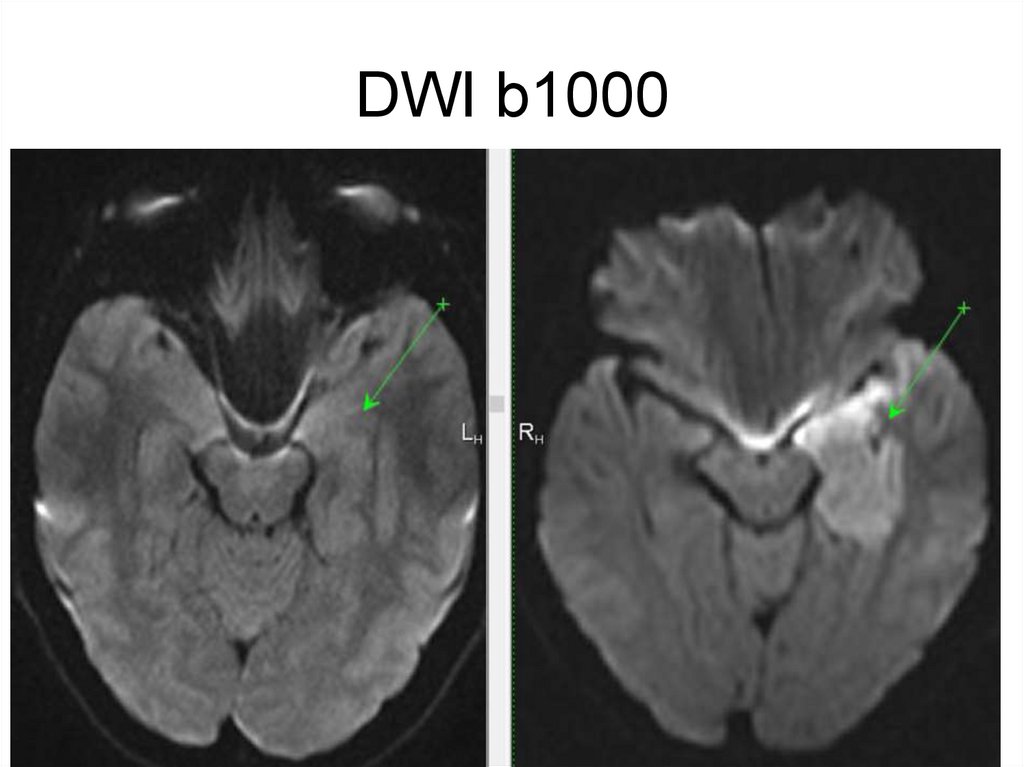

DWI b1000

4.